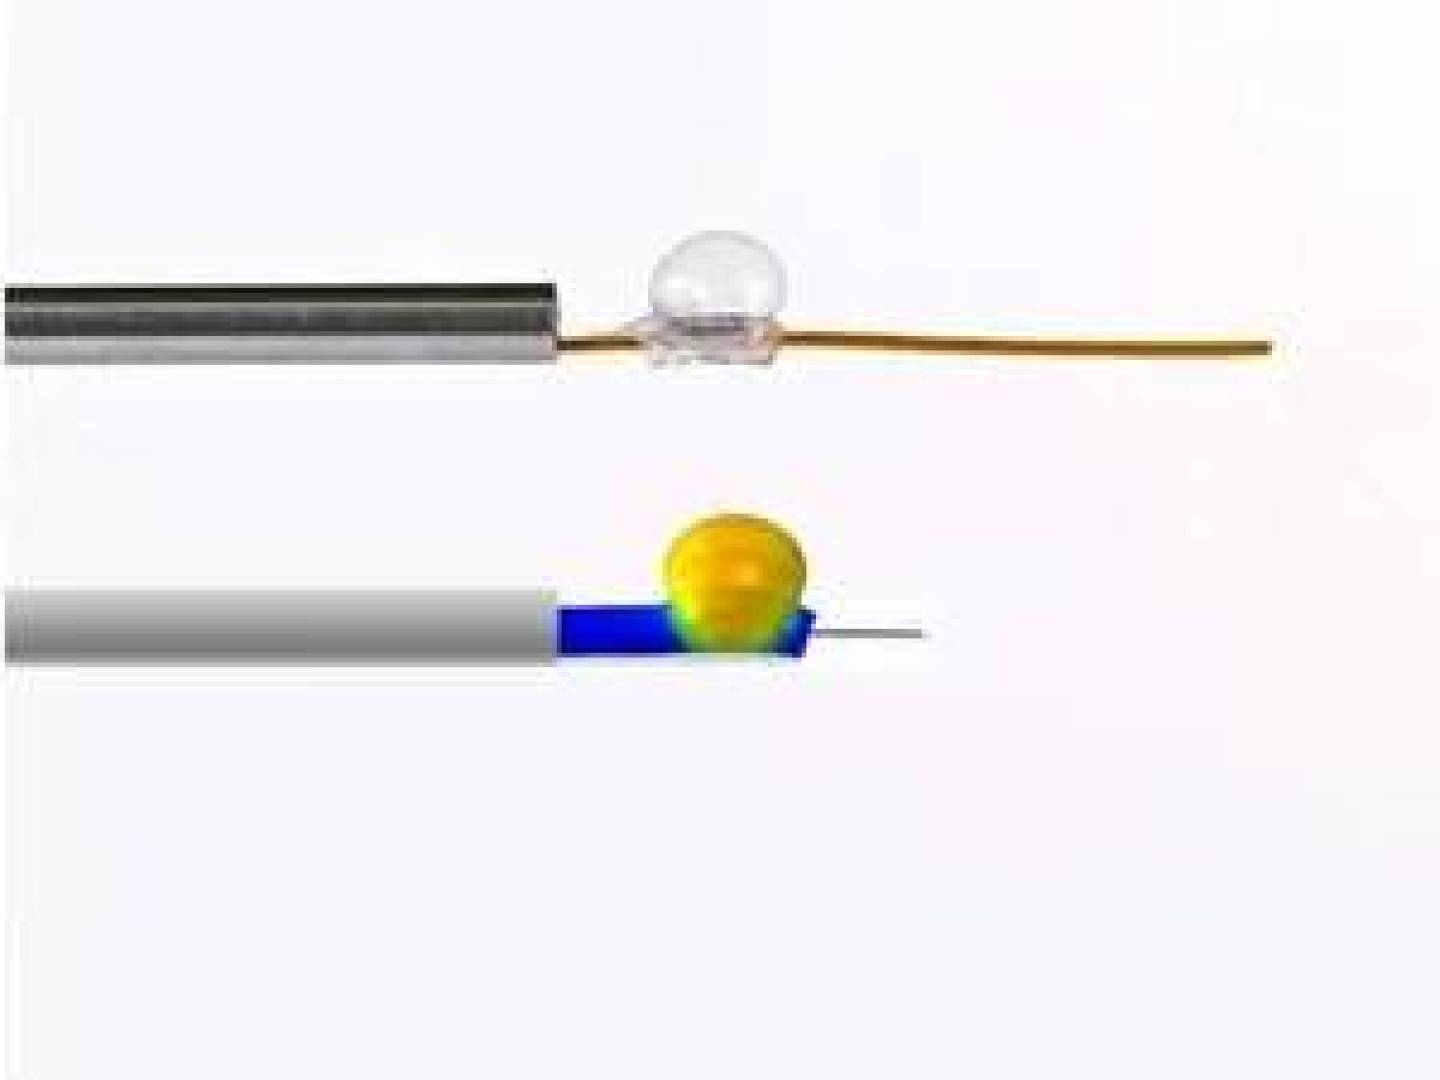

ابتكار مسبار طبي لمراقبة الجنين أثناء العمليات الجراحية داخل الرحم

تمكّن باحثون من تطوير أول مسبار طبي في العالم يسمح بمراقبة حالة الجنين بشكل مباشر أثناء العمليات الجراحية داخل الرحم، وهي إجراءات…